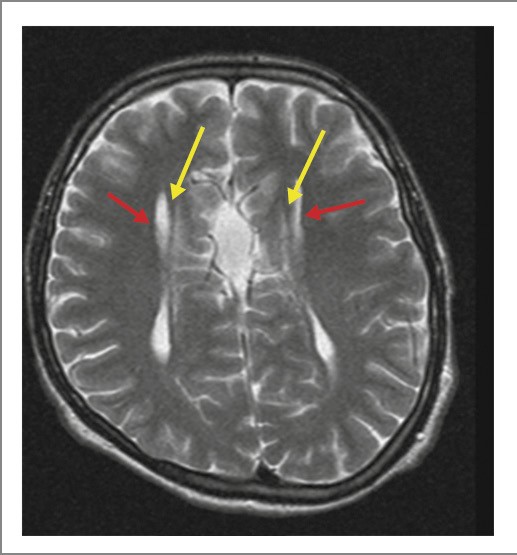

Рис. 3. Больной Б., 12 лет. МРТ ГМ: Т2-взвешенное последовательное изображение в аксиальной плоскости: симптом «гоночного автомобиля» – расширенное расстояние между латеральными желудочками (красные стрелки); миелинизированные пучки Пробста располагаются медиальнее боковых желудочков (желтые стрелки).

Визуализируются пучки Пробста. Гиппокамп закруглен в аксиальных срезах. Боковые желудочки имеют параллельный ход, расстояние между ними – 44 мм, III и IV желудочки не расширены.